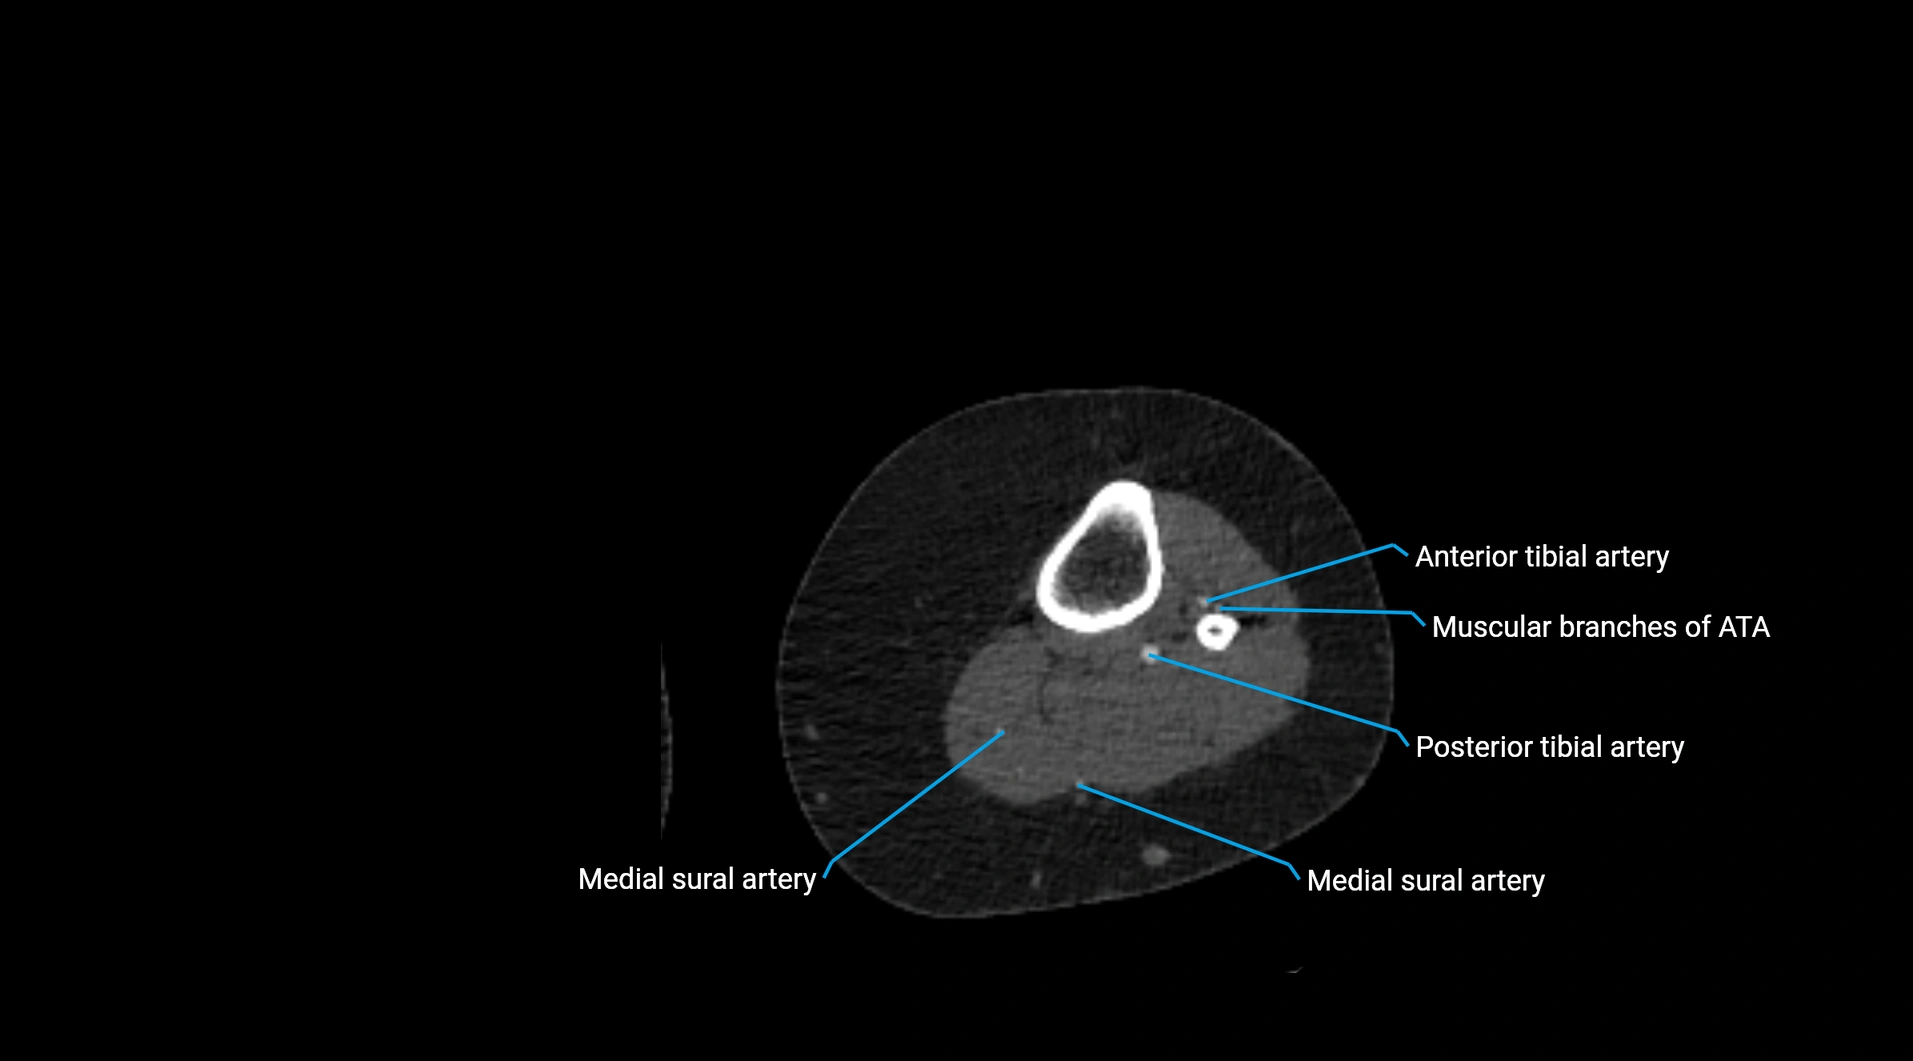

Contrast-enhanced CT (CTA):

• Gold standard for abdominal aortic imaging

• Provides excellent detail of lumen, wall, aneurysm, thrombus, and branch vessels

• Multiplanar and 3D reconstructions help in aneurysm measurement, stent graft planning, and dissection evaluation

• Detects acute rupture, traumatic injury, or occlusion with high sensitivity